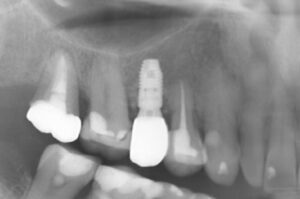

骨のない部分を骨造成し、インプラントを入れた症例

著しく骨が吸収されていたため、そのままインプラントを入れることはできない

人工骨を使った骨造成術を行い骨が再生するのを半年程待ち、インプラントを入れた

骨造成術、インプラント手術ともに術後の痛みや腫れもなく順調に経過し、治療後のレントゲン画像でも十分な骨の再生が認められる。